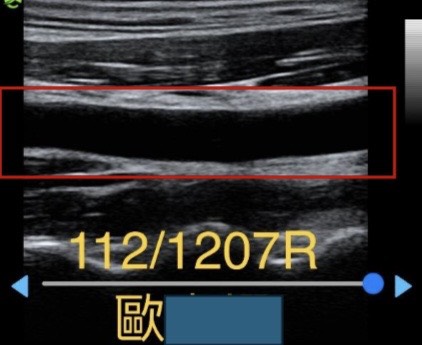

三個月後回診,檢查結果,右側頸動脈幾乎無阻塞,血管中間幾乎無白色雜質,乾乾淨淨。抽血報告 : 血糖,血脂,血壓皆正常。 肝,腎功能正常。

破除長久吃中藥會傷腎的疑慮。

病人自訴自服中藥以來,十年以上的久年頭暈三個月即有明顯改善,很少再發生,神清氣爽,工作效率提升,急躁易怒的脾氣也溫和許多( 老婆認證 )。也順利戒除吃了20年以上的安眠藥,也能安穩好眠一整夜。恭喜患者重拾有品質的生活。